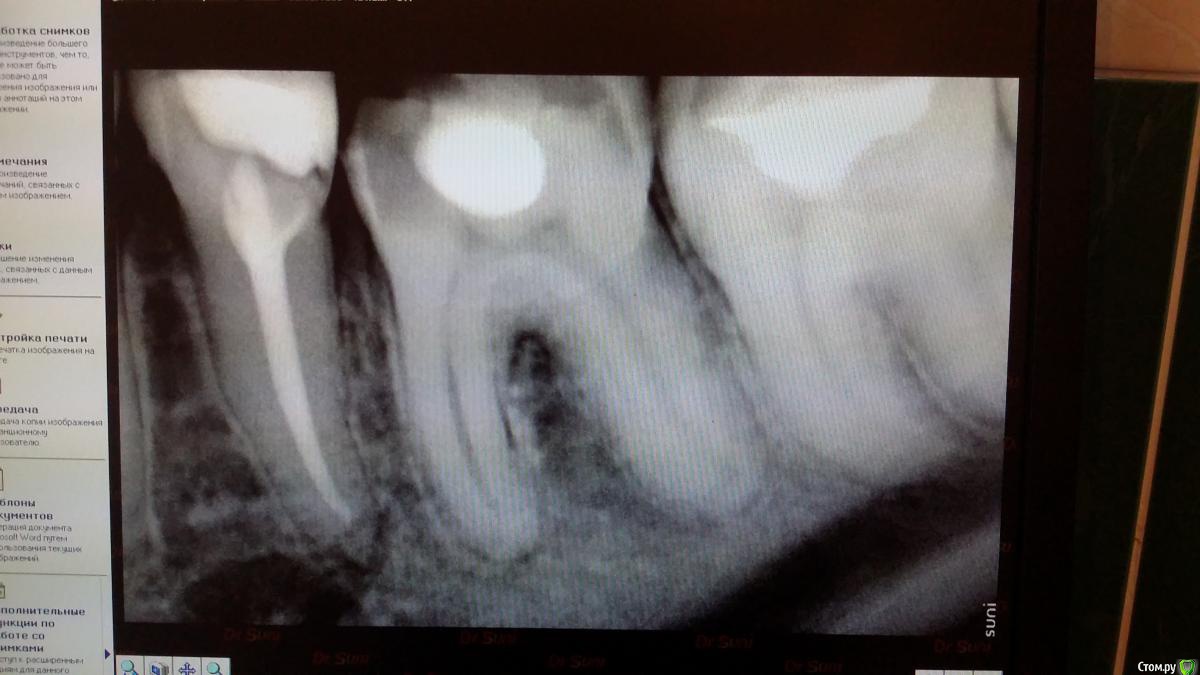

Recive Опубликовано 9 февраля, 2015 Поделиться Опубликовано 9 февраля, 2015 Жалобы: классический пульпит./периодонтитанамнез:эндэндодонтия первичнаялечение:ммо кк первое посещение пульперил, да не будет больеть! Аминь)Второе- в мщ, мя каласепт в дистальном метапаста (ннагнитал каналонаполнителем в надежде найти дельту в апексе)Третье - через неделю замена каласепта на каласепт, и в дистальный крезофен, для надежности.Четвертое на 16.02 пломбировать если не будеет болеть. Ваше мнение и варианты .первый снимок при поступлениивторой при прохождениивторой контроль метапасты и каласепта1.02. 09.02. 1 1 Ссылка на комментарий

Catherine Опубликовано 11 февраля, 2015 Поделиться Опубликовано 11 февраля, 2015 Может быть, это последствия трудного трудового дня, но мне на первом снимке в дистальном отделе вообще две верхушки видятся... Ссылка на комментарий